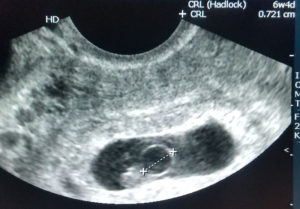

В исследованиях главным показателем является средний и внутренний диаметр плодного яйца (СВД). О сроке беременности судят по размеру имеющегося плодного яйца, которое в первые недели должно быть овальной или сферической формы. Это норма.

УЗИ показывает врачу не только форму, но и патологии, которые могут быть вызваны при этом. Например, уже на 6 неделе можно спрогнозировать замирание беременности.

Ультразвуковое исследование позволяет специалисту выявить размеры яйца по внутренним контурам. Вообще, плодное яйцо на УЗИ рассматривается в том числе с целью определения диаметра. Однако данные измеряются с некоторыми погрешностями, которые составляют одну-две недели. Именно это и является причиной того, что доктор ставит срок беременности не тот, который поставила сама мамочка.